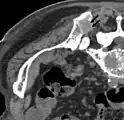

Scanner d'une métastase ostéocondensante dans l'os du crâne d'un patient souffrant d'un carcinome de la prostate. On reconnaît clairement l'extension de la métastase au-delà des limites initiales de l’os.

Scanner

La tomodensitométrie, ou tomographie axiale calculée par ordinateur est pratiquée le plus souvent après la radio X conventionnelle et la scintigraphie. Dans ces procédés d'imagerie, on détermine les domaines qui doivent être représentés par le scanner avec une résolution bien plus fine, et une meilleure qualité. Le scanner donne des informations sur la mesure de la destruction de l'os et la stabilité du domaine touché par les métastases osseuses[87]. Ces informations sont de grande importance pour la planification du traitement, en particulier pour des interventions chirurgicales éventuelles.

L'indication pour un examen au scanner est donc avant des interventions opératoires stabilisantes (par exemple une excision vertébrale), avant une biopsie (quand la lésion est visible en scintigraphie, mais pas en radio) ainsi que dans le cas de fractures menaçantes ou déjà survenues[87].